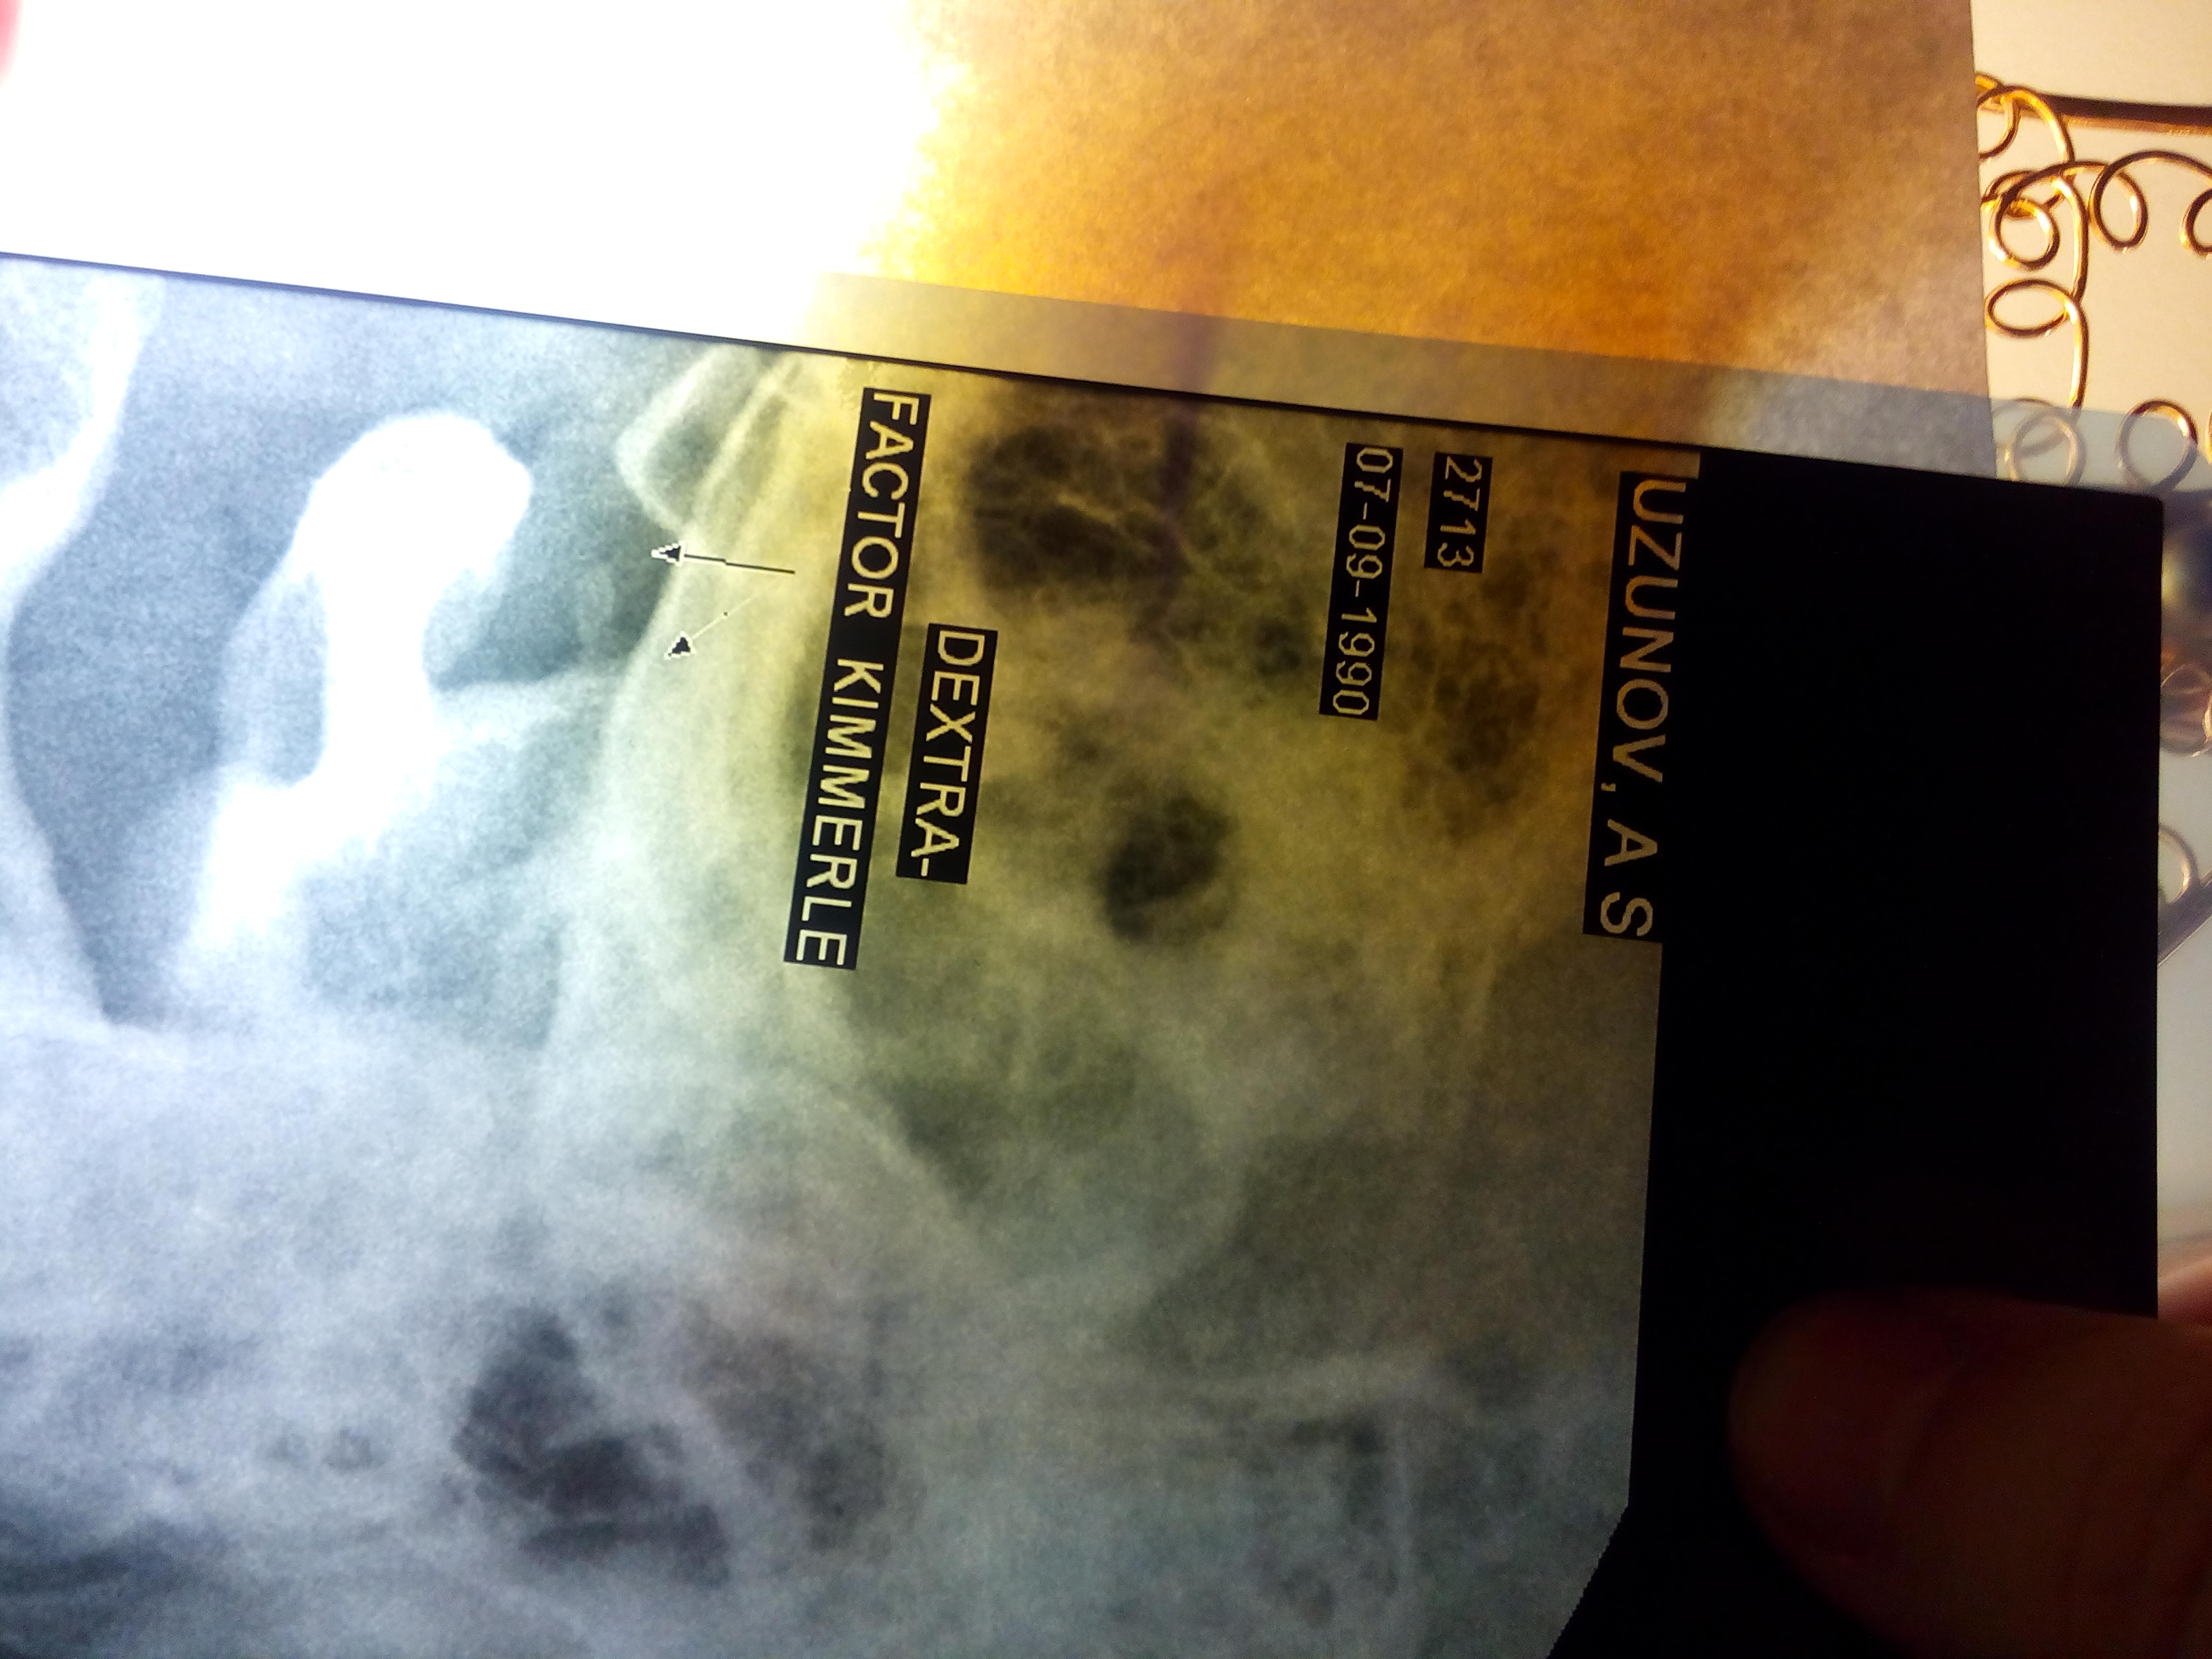

P.S. прилагаю снимки аномалии (простите за качество, я фотографировал снимки)

Снимок Кимерли 2015 г..jpg

Снимок Кимерли (2) 2015 г..jpg

Рентген 2015 (АНОМАЛИЯ).jpg

про снимки-аномалия не убедительна и ,как говорил, кт в данном случае более показателен.